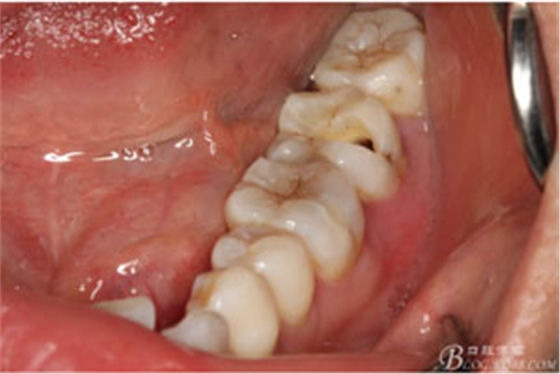

圖3.取出棉球口內(nèi)發(fā)現(xiàn)37合面有開(kāi)髓孔,探針出血,頰側(cè)牙齦紅腫